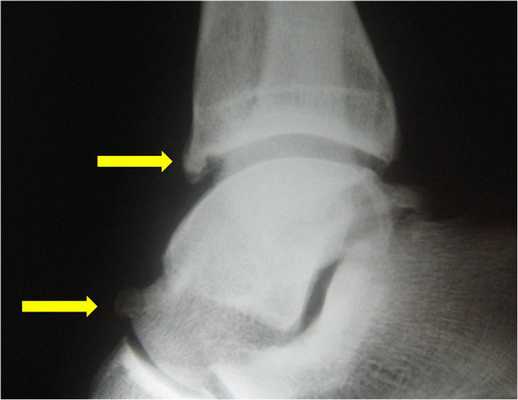

- На рентгенограммах с нагрузкой в боковой проекции могут быть видны остеофиты большеберцовой и таранной костей. В переднем завороте могут быть свободные суставные тела, могут быть признаки перелома остеофитов (рис. 1, А):

• Магнитно-резонансная томография (МРТ) позволяет увидеть выпот в переднем отделе голеностопного сустава, синовит, а также остеофиты (рис. 1, Б). Может быть видна гипертрофированная связка Бассетта (рис. 1, В)